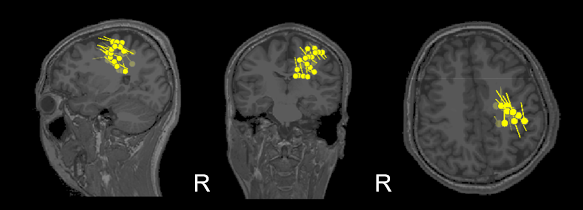

该名癫痫患者此前多次脑影像检查均未能明确病灶位置,术前评估陷入僵局。为完善术前评估,我院脑磁图成像中心为其进行了1小时的静息态MEG数据采集。结果显示,MEG不仅清晰捕捉到棘波样放电(图1),且将病灶溯源定位于左侧脑区(图2),为后续手术提供了关键依据。

图2 棘波溯源结果

基于MEG的定位结果,兰大二院神经外科团队进一步对患者进行了颅内立体脑电图(sEEG)监测,结果证实MEG提示的阳性区域确实存在持续性棘波痫样放电。兰大二院神经外科主治医生表示:“本次术前评估因MEG的参与更趋完善,尽管病情复杂,但定位更接近疾病本质。”在明确致病灶位置后,患者接受了微创热凝毁损手术。术后患者恢复良好,反馈积极,后续将进行长期随访以评估远期疗效。